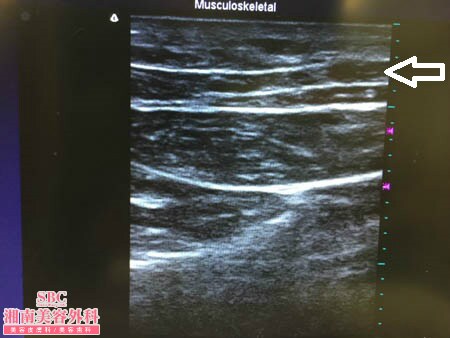

No.178149【脂肪吸引】他院での脂肪吸引の経験を活かして今回は竹田先生に根こそいでもらう!腰術中3Dタッチビュー

腰術中3Dタッチビュー

今回は腰の脂肪吸引の術中の模様を

紹介したいと思います。

いつものように3Dタッチビューから。